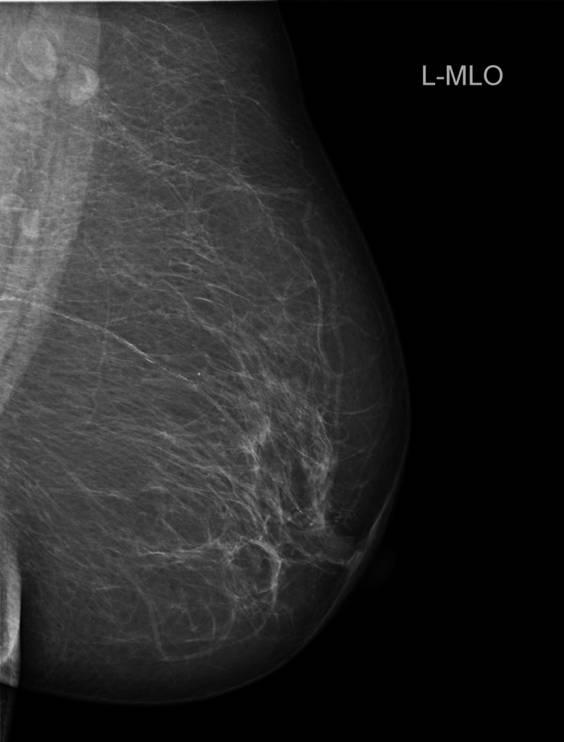

Mammografi. Samme kvinde som ovenfor, venstre bryst.